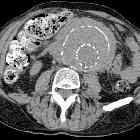

CT

Retroperitoneal fibrosis is visible as a soft tissue density mass located around the aorta and iliac arteries. Classically, it develops around the aortic bifurcation and spreads upwards where it can envelop the renal hila. It encases but does not invade or stenose the ureters or vessels. However, ureteric obstruction and venous thromboses can occur.

In early or active stages, variable enhancement can be seen with intravenous contrast while no enhancement may be seen in the quiescent disease.